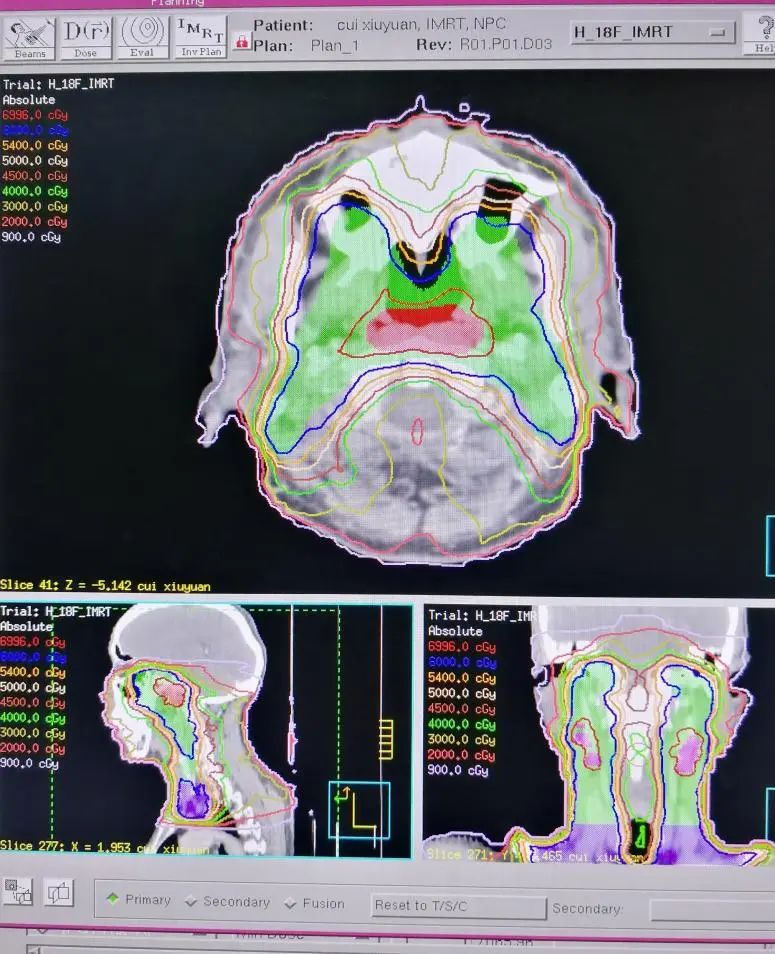

放疗物理师根据放疗申请单的要求,在专用的放疗计划系统里制定放疗计划,通过布野、设置各种各样的参数、优化、计算,从而实现放疗靶区达到处方剂量的要求,同时保护好周围的正常器官。制定一个好的放疗计划通常需要几小时几天时间不等,具体的时间由计划的复杂程度、放疗系统的优化速度、采用的何种放疗技术、工作人员的经验等多方面因素决定。比如,一个鼻咽癌的放疗计划,因为需要保护的危及器官太多,复杂程度远远高于一个全脑放疗计划,所用时间自然也会更多。一个放疗计划制定好以后,一般是要用这个计划给患者治疗整个疗程的,所以计划设计的重要性也就不言而喻了。

放疗计划制定好以后需要有放疗资质的、经验丰富的放疗医师与物理师一同来确认计划。按照治疗规范、指南的要求来审核计划,看各个危及器官的受量是否在安全范围内,看放疗靶区的剂量是否达到要求,并确定签字,同时记录在放疗病历上。